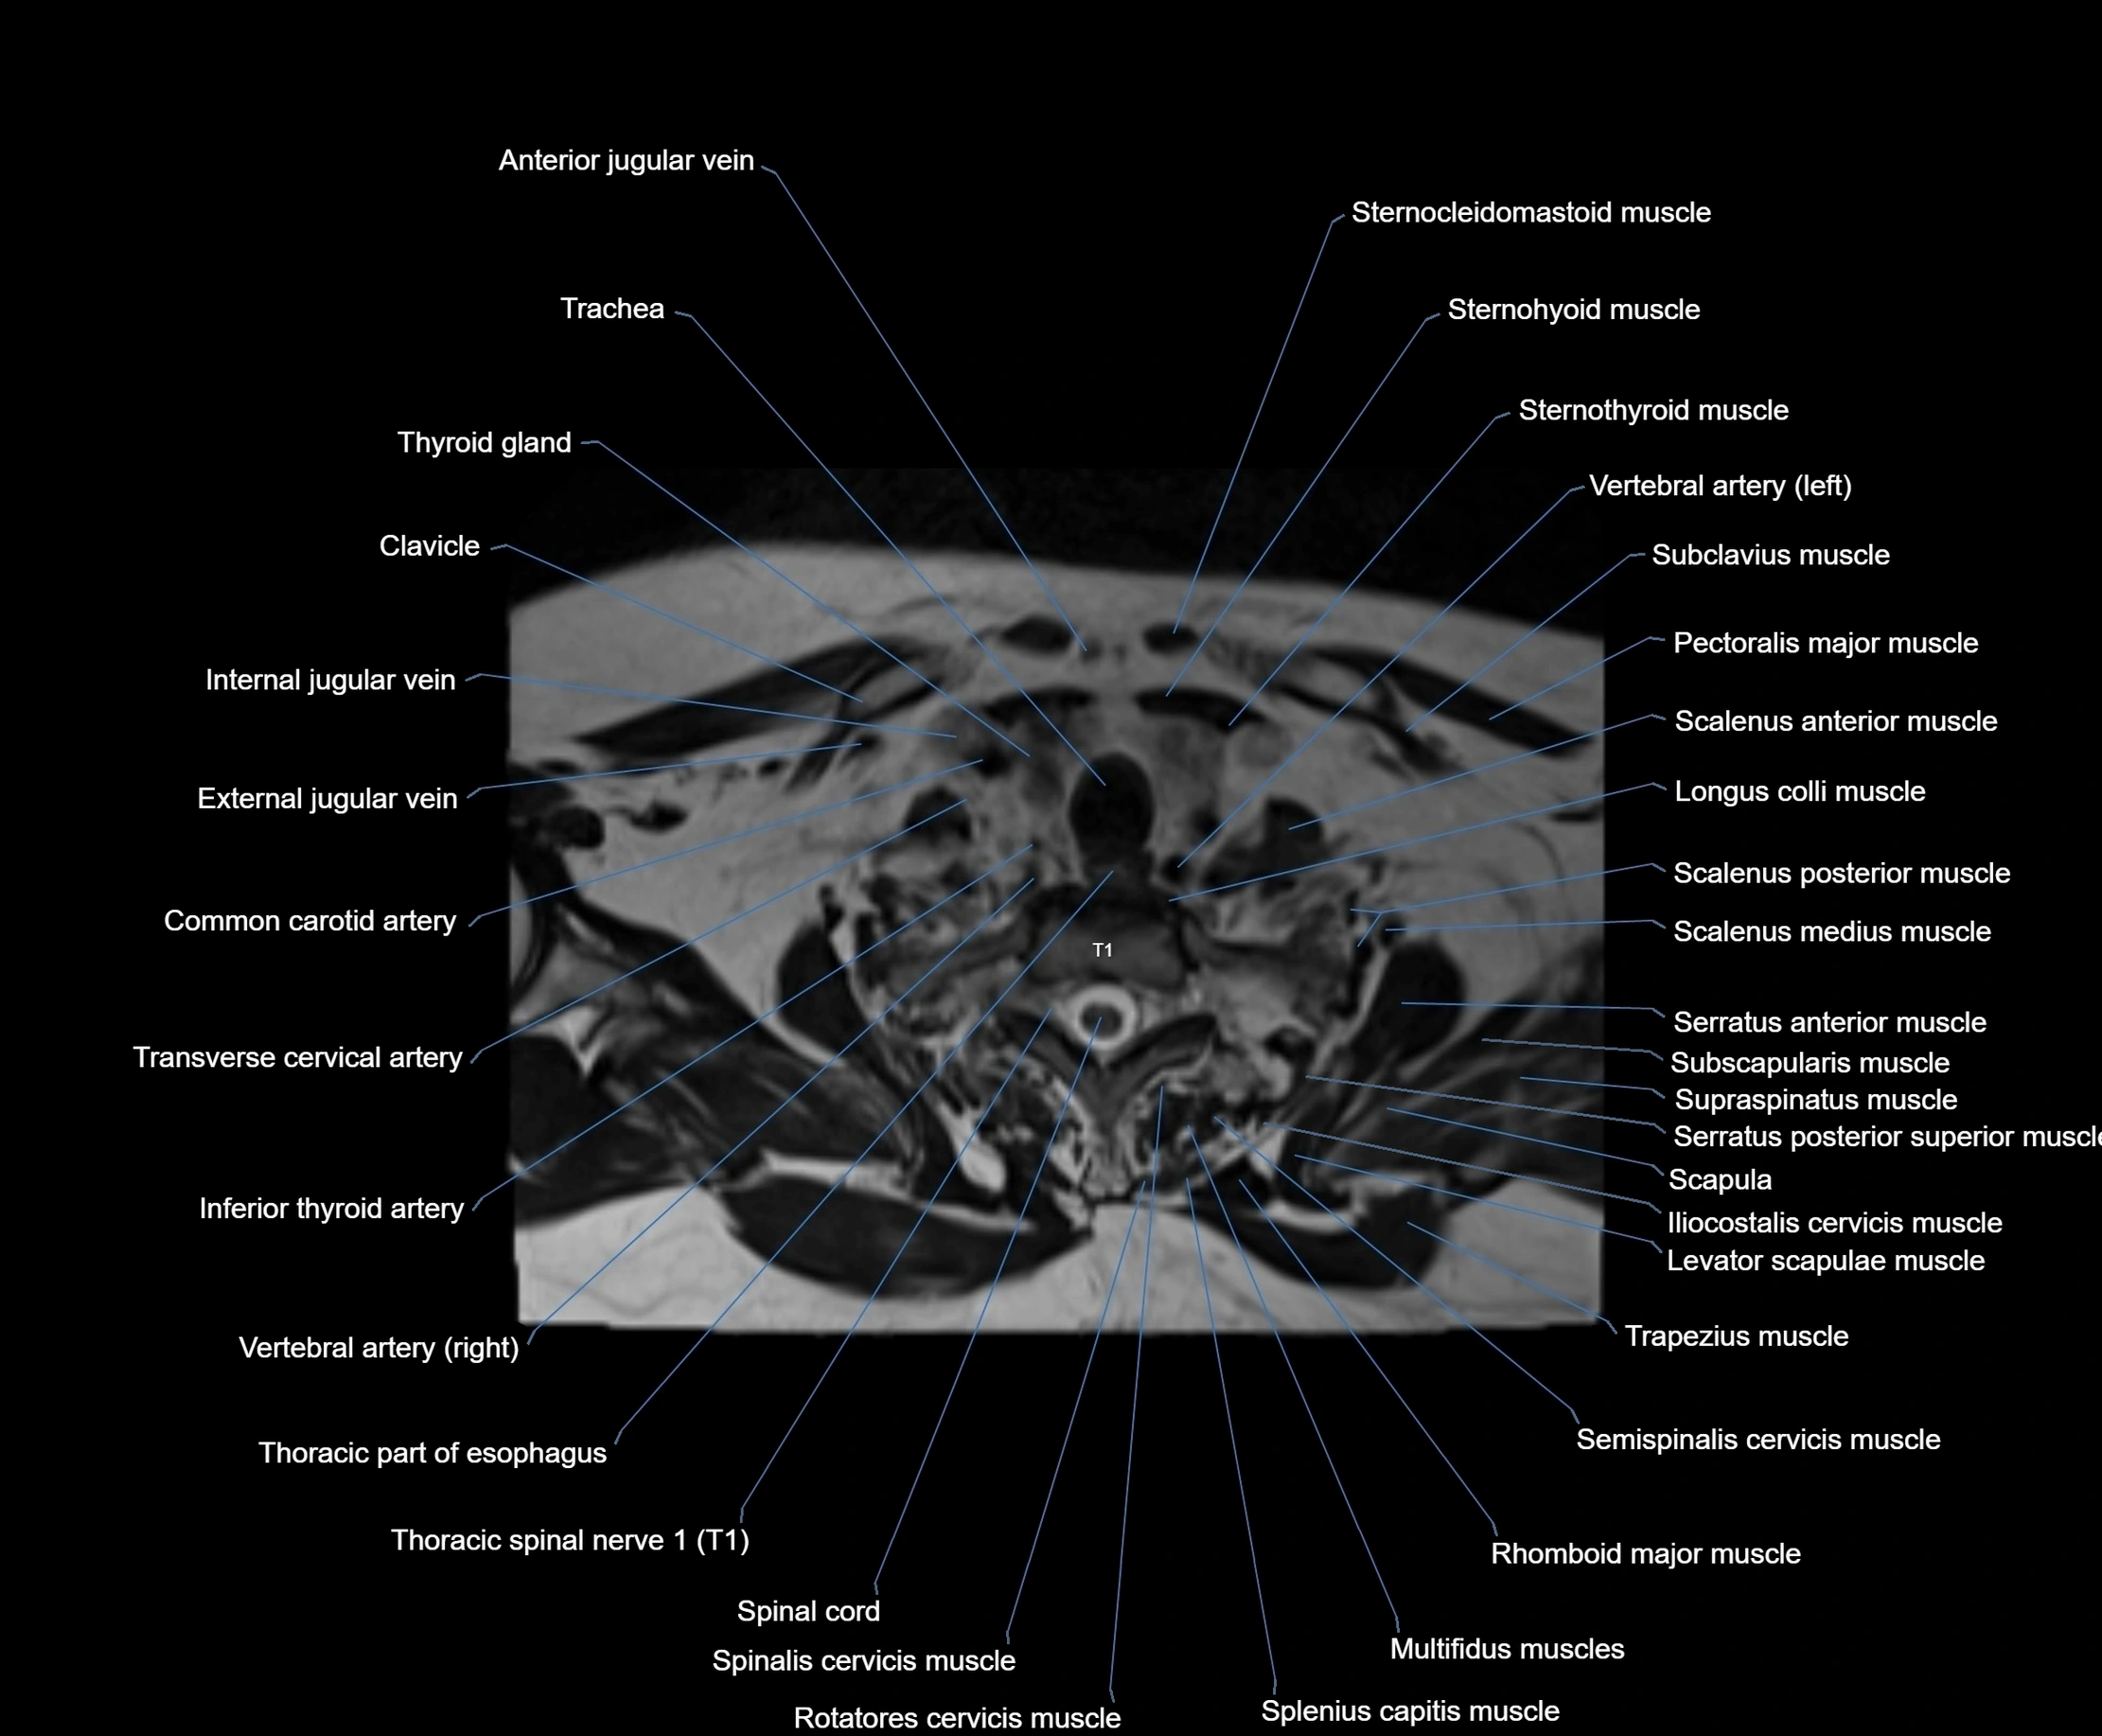

MRI images